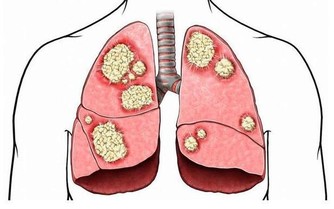

痛風的人都是有著高尿酸血,對於高脂的飲食是需要避免的,因為高脂飲食可能會導致尿酸排出的減少,從而可能會加重病情的,而花生中就含有大量蛋白質、脂肪,也屬於中等嘌呤含量的食物,特別是痛風急性發作期的時候,應該禁止食用花生的。